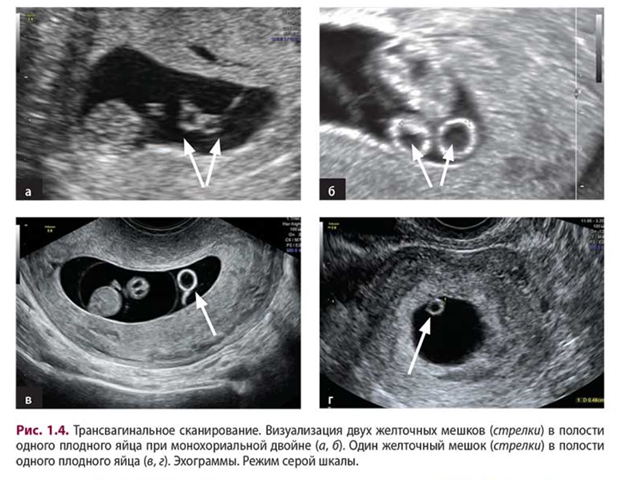

Визуализация межплодовой перегородки позволяет разделить монохориальные двойни на:

* Диамниотические: Перегородка визуализируется.

* Моноамниотические: Перегородка отсутствует, высокий риск переплетения пуповин (требует интенсивного мониторинга).